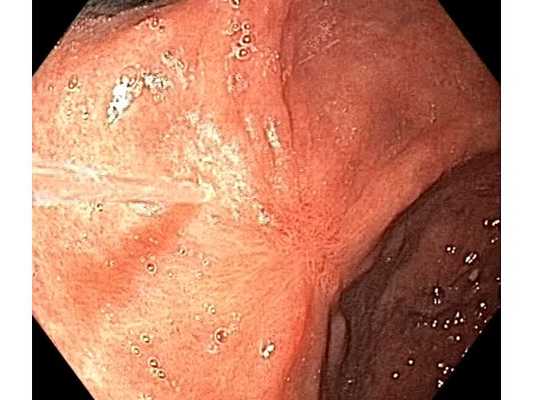

После подготовки раствором Симетикона больному выполнили видеогастроскопию с помощью оборудования экспертного класса, которое может увеличить изображения и выполнить цифровую хромоскопию, что позволяет выявить мелкие поражения слизистой оболочки. При обследовании у пациента диагностировали:

- гиперпластический полип желудка размером 8 мм;

- плоско-углублённую опухоль размером 10×8 мм в выходном отделе желудка на фоне воспаления слизистой.

Опухоль имела чёткие границы и при тщательном осмотре рельеф поверхности и сосудистый рисунок слизистой позволили заподозрить раннюю стадию злокачественного процесса.